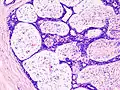

| Histopathologic image of breast fibroadenoma. Core needle biopsy. H&E stain. | |

Fibroadenoma Histology (H&E). The image demonstrates intracanalicular morphology (bottom left) and pericanalicular morphology (top right)

Histopathologic image of breast fibroadenoma. Core needle biopsy. Hematoxylin & eosin stain.

Histopathologic image of breast fibroadenoma showing proliferation of intralobular stroma compressing and distorting the epithelium. H&E stain.